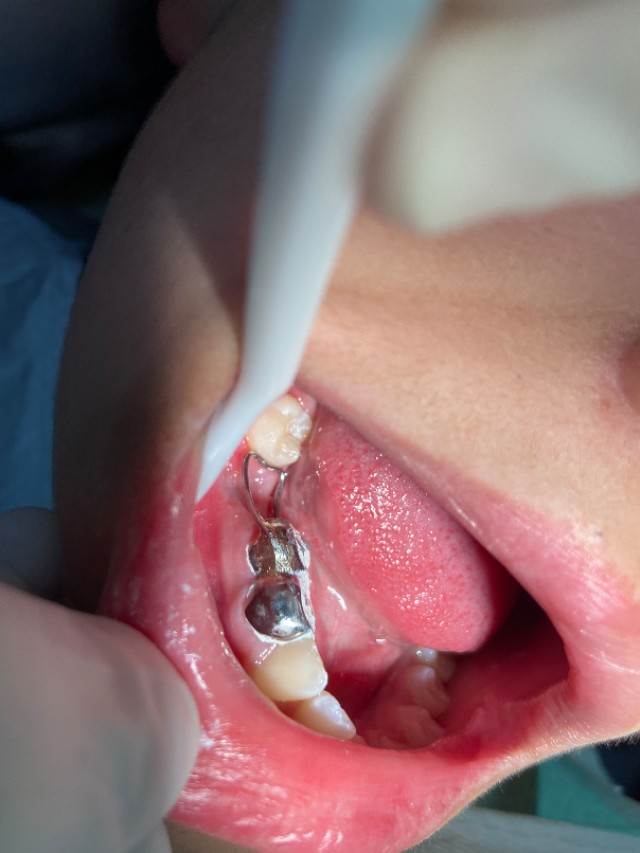

那就是今天我要讲的一个东西叫“间隙保持器”。

顾名思义,就是保持牙间隙的东西。替后期镶牙占着空间。不至于出现成年后镶牙没有位置的尴尬情况。

戴上它,就完美解决这个问题啦!